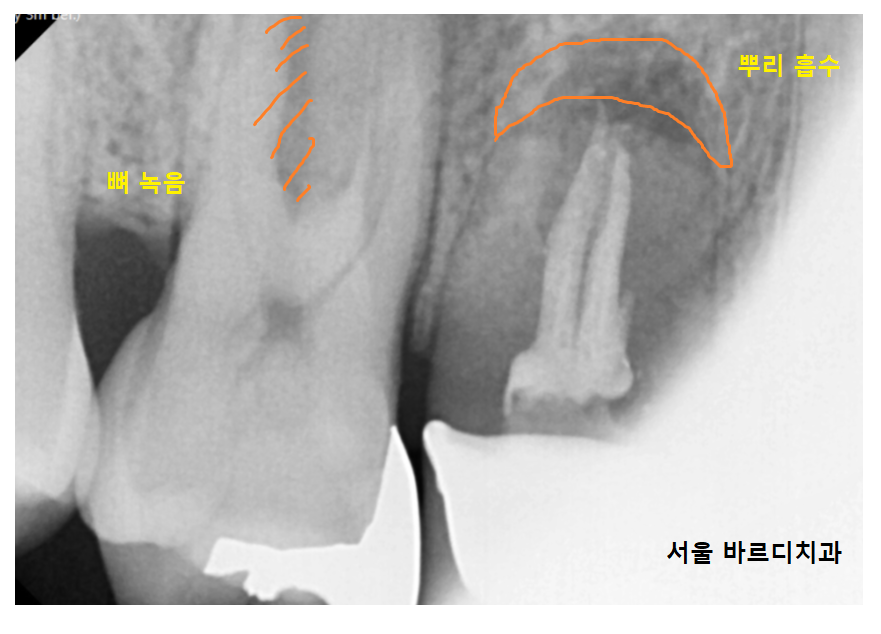

ct를 한번 찍어보았습니다.

23.03.29

치아 뿌리가 갈라지는 부위도 보이고

뿌리가 녹으면서 뼈에 웅덩이 파이듯

구멍 뚫린게 보이네요ㅠㅠ